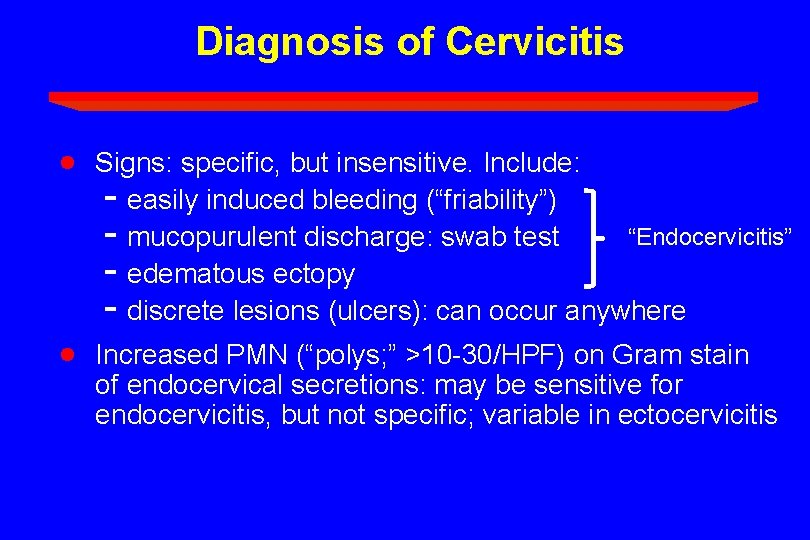

Diagnosis of Cervicitis · · Signs: specific, but insensitive. Include: - easily induced bleeding (“friability”) “Endocervicitis” - mucopurulent discharge: swab test - edematous ectopy - discrete lesions (ulcers): can occur anywhere Increased PMN (“polys; ” >10 -30/HPF) on Gram stain of endocervical secretions: may be sensitive for endocervicitis, but not specific; variable in ectocervicitis